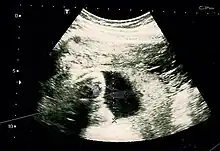

Suspicion of an abdominal pregnancy is raised when the fetal anatomy can be easily felt, or the lie is abnormal, the cervix is displaced, or there is failed induction of labor.[1] X-rays can be used to aid diagnosis.[11] Sonography can demonstrate that the pregnancy is outside an empty uterus, there is reduced to no amniotic fluid between the placenta and the fetus, no uterine wall surrounding the fetus, fetal parts are close to the abdominal wall, the fetus has an abnormal lie, the placenta looks abnormal and there is free fluid in the abdomen.[8][18] MRI has also been used with success to diagnose abdominal pregnancy and plan for surgery.[16][19] Elevated alpha-fetoprotein levels are another clue of the presence of an abdominal pregnancy.[20]

Most cases can be diagnosed by ultrasound.[21] The diagnosis however may be missed with ultrasound depending on the operator's skill.[7][22]